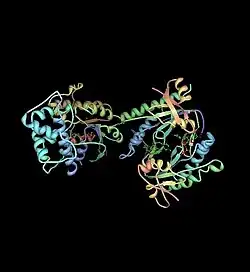

Die FD wird durch eine nichtvererbbare Mutation des G-Proteins ausgelöst (im α-subunit). Die Mutation befindet sich im Gen GNAS (oder auch Gsα-Gen) des 20. Chromosoms. G-Proteine sind im Stoffwechsel der Zellen für die Signalweiterleitung extrem wichtig. Durch die Mutation kommt es zu einer Überaktivierung des Enzyms Adenylylcyclase, das die Katalyse von ATP zu cAMP steuert (das ist dann der eigentliche Signalübertragungsprozess). cAMP regelt z. B. die Herzfrequenz, Relaxation der glatten Muskulatur, die Wirkung von zahlreichen Hormonen und eben auch die Knochenzellen, die für den Aufbau von Knochen verantwortlich sind (Osteoblasten). Der Grund für diese Mutation ist noch unbekannt. Sie kann bereits im Föten-Stadium während der Schwangerschaft auftreten (dann treten die Symptome bereits im Kindes- und Jugendalter auf) oder auch erst später, nach der Geburt. Da die FD sehr stark mit Hormon- und anderen Zellstoffwechselprozessen verbunden ist, kann sie nach der Pubertät aufhören. An den eingetretenen Deformitäten ändert das nichts.